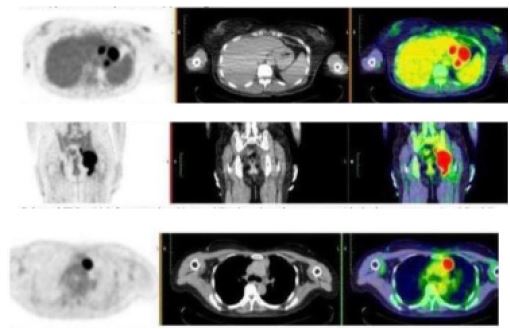

A Positron Emission Tomography (PET) CT was also performed for staging and further work-up, showing the following hypermetabolic lesions: enlarged pre-vascular lymph node, diffuse enhancing gastric wall thickening, enlarged perigastric lymph nodes, lobulated enhancing left pelvic side wall mass with erosive changes in the adjacent left ischium and acetabulum, enlarged left external and internal iliac lymph nodes and enlarged lymph node between the left pectineus and adductor muscles (Figure 5).

Figure 5: PET CT scan showing hypermetabolic lesions.

During the fourth month follow-up, no recurrence of the hyper metabolic lesions was observed as seen on the repeat PET CT scan (Figure 6) showing complete metabolic response with no hyper metabolic nodal disease and interval disappearance of the enlarged lymph nodes/mass in the chest, abdomen and pelvis. There was interval resolution of the diffuse enhancing gastric wall thickening showing good treatment response. Until present, our patient is in complete remission.

Image is Not Display Check it

Figure 6: PET CT scan showing complete metabolic response with no hyper metabolic nodal disease and interval disappearance of the enlarged lymph nodes/mass in the chest, abdomen and pelvis.

Whole-body FDG PET/CT (11/28/22)

- Enlarged prevascular lymph node

- Diffuse enhancing gastric wall thickening

- Enlarged perigastric lymph nodes

- Lobulated enhancing left pelvic side wall mass with erosive changes in the adjacent left ischium and acetabulum

- Enlarged left external and internal iliac lymph nodes

- Enlarged lymph node between the left pectineus and adductor muscles

Whole-body FDG PET/CT (4/14/23)

Complete metabolic response with no hypermetabolic nodal disease and interval disappearance of the enlarged lymph nodes/mass in the chest, abdomen and pelvis. Interval resolution of the diffuse enhancing gastric wall thickening. Known case of high-grade B-cell Lymphoma, s/p 6 cycles chemotherapy showing good treatment response.